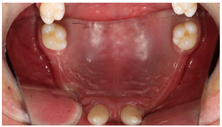

口外检查:颜面部表情自然,意识清楚,无关节弹响压痛,无张口受限,开口4.5cm,最大辅助开口5cm。面部左右不对称,颏点右偏,开口右侧偏斜。口内检查:上颌余留#17,11,21,27,畸形牙;下颌全口牙缺失,牙槽嵴萎缩,角化龈萎缩。唇部肌肉对抗牵拉力量较强,前庭沟浅(图4,图5,图6)。

辅助检查:3D打印上下颌骨模型,可见上颌缺牙区域剩余牙槽嵴菲薄,颧骨厚度不佳,下颌颏孔靠近牙槽嵴顶,牙槽嵴顶向内吸收,咬合空间尚可(图7)。